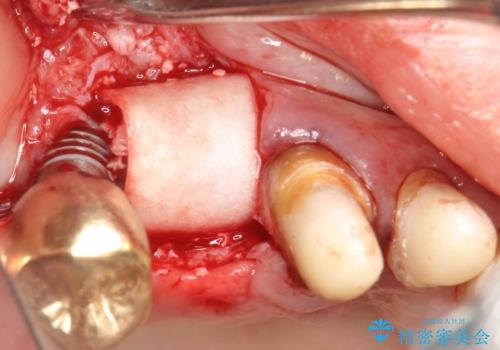

骨が薄く、インプラントの径に耐え得ないと判断したためスプリットクレストにより骨幅を拡大しインプラントを埋入した。

スプリットクレストやリッジエキスパンジョンといった方法は、骨が薄く、細い場合に、割線を設定し、狭い骨幅を拡大すると同時にインプラントを埋入することができます。

インプラントの種類:Bicon